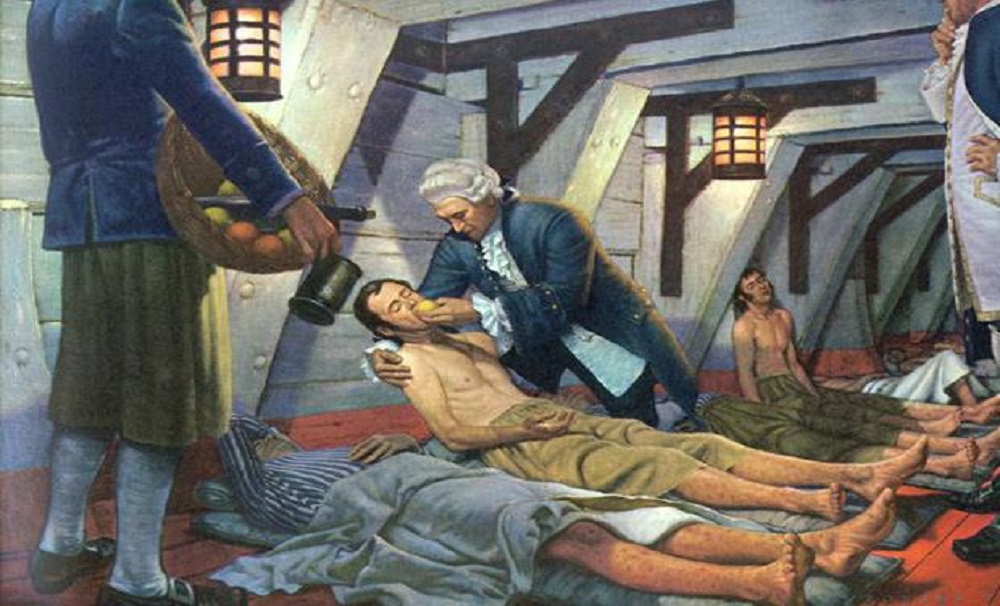

Potato keeps you away from Scurvy disease

Scurvy is a feared deficiency disease which is caused due to lack of Vitamin C. So, eating potato can stop this disease as potato is rich in Vitamin C. If potato has so many benefits then why is it often avoided to remain healthy? It is so because potato is not bad for our health; it is the topping and preparation method that turns a healthy potato into fatty and salty snack. So, avoid to eat potato chips, finger chips etc., instead you should eat steamed potatoes.